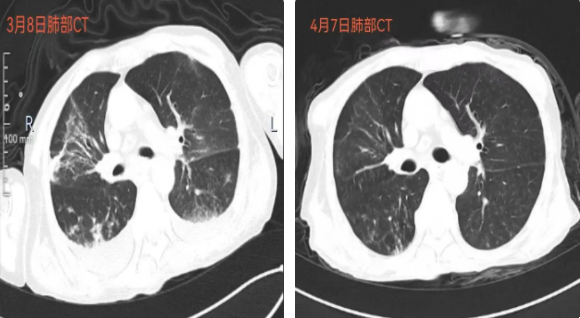

经过一段时间的治疗,患者意识逐渐清楚,咳痰能力增强,肺部感染得到控制,痰液明显减少,吞咽功能也得到了改善。樊永梅主任针对患者气管拔管的指征进行了专业评估,经过堵管试验后,患者于3月20日顺利拔除气切套管,3月28日顺利拔除胃管。